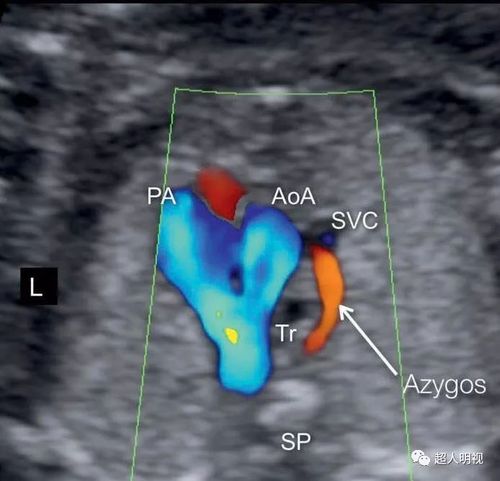

胎儿三血管气管切面

胎儿三血管气管切面,胎儿静脉导管解剖

异常篇:三血管气管切面——胎儿心超最重要的切面

正常篇:三血管气管切面——胎儿心超最重要的切面

充分理解胎儿三血管气管切面(正常篇)

三血管气管切面

三血管气管切面异常

胎儿心脏三血管切面